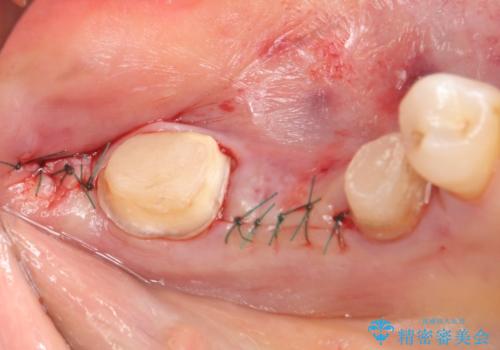

左下7の遠心部は部分的な骨欠損によるポケットが10mmあったため、再生療法による骨の再生を行いました。

骨の定着を待ちポケットが3mm(正常範囲内)であることを確認後、オールセラミッククラウンによる欠損補綴を行いました。

再生療法とは歯槽骨の欠損部位を人工骨で補うことにより骨を再生させる手術です。

この手術を行うことで、歯周基本治療では治癒しない歯周病を改善したり、本来ならば抜歯しなければならない歯を保存することができます。